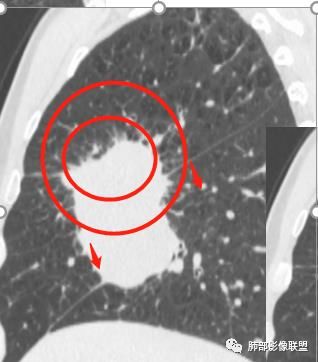

我有一个疑问,这个病灶一开始到底起源于哪一个叶?

可以看到斜裂一侧往上一侧往下,那么就是说病灶应该是起源中叶,往上,往下侵犯这样

是这样吗?

@吴婧南京市第一医院 主体应该还是中叶

往下叶这个地方是突然就鼓出来了,这个地方还是应该叶裂缺限。

如是上叶的,叶间裂的方向应该是往一侧压得

不是上叶

只有这个位置起源得才能做到,将叶间裂上下往不同方向推

斜裂向下推移了,水平裂向上推移了。

@吴婧南京市第一医院 这个从影像表现,坏死情况,以及叶裂推移情况与支气管推移情况来看,还是支持中叶间质来源,外朝内生长,同时向上,向下,向内都有推移作用。

下半段斜裂推移朝下

水平裂推移朝上

定在中叶应该没问题

深分叶

是的,中叶基本肯定。

嗯,主体在中叶

上叶应该是侵犯,下叶应该是叶裂漏出来的。